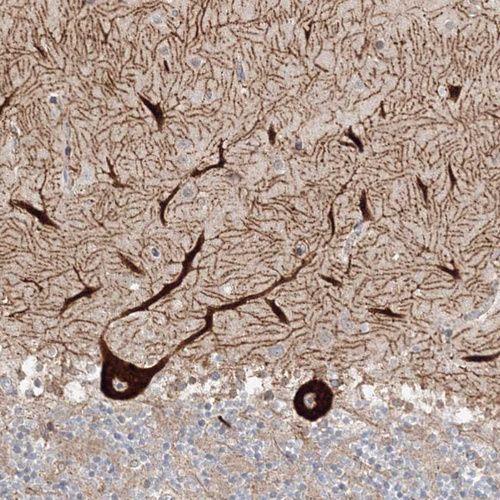

Immunohistochemistry analysis in human cerebral cortex and duodenum tissues using HPA034609 antibody. Corresponding HECW2 RNA-seq data are presented for the same tissues.